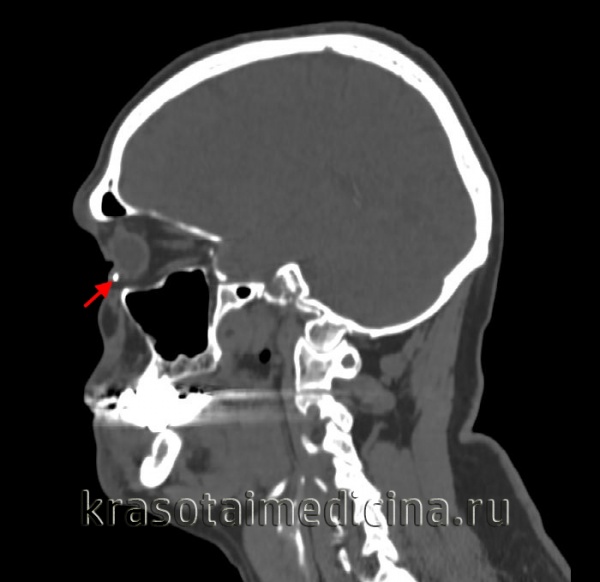

- Оптическая когерентная томография. Методика ОКТ проводится для уточнения диагноза, если по результатам биомикроскопии остались сомнения в характере травмы. При глубоком поражении тканей глаза назначают КТ глазниц, которая позволяет исключить поражения близлежащих анатомических структур.

Основными методами выявления инородных тел глазницы служат рентгенография орбиты, рентгенография придаточных пазух носа, рентгенография костей черепа. При необходимости ведение пациента с инородным телом глаза осуществляется офтальмологом совместно с отоларингологом и неврологом.

Распознавание характера и степени тяжести механических повреждений глаз производится с учетом анамнеза, клинической картины травмы и дополнительных исследований. При любых травмах глаза необходимо проведение обзорной рентгенографии орбиты в 2-х проекциях для исключения наличия костных повреждений и внедрения инородного тела.

Пациенты с механическими повреждениями глаз должны быть проконсультированы хирургом-офтальмологом, неврологом, нейрохирургом, отоларингологом, челюстно-лицевым хирургом. Дополнительно может потребоваться проведение рентгенографии или КТ черепа и придаточных пазух.